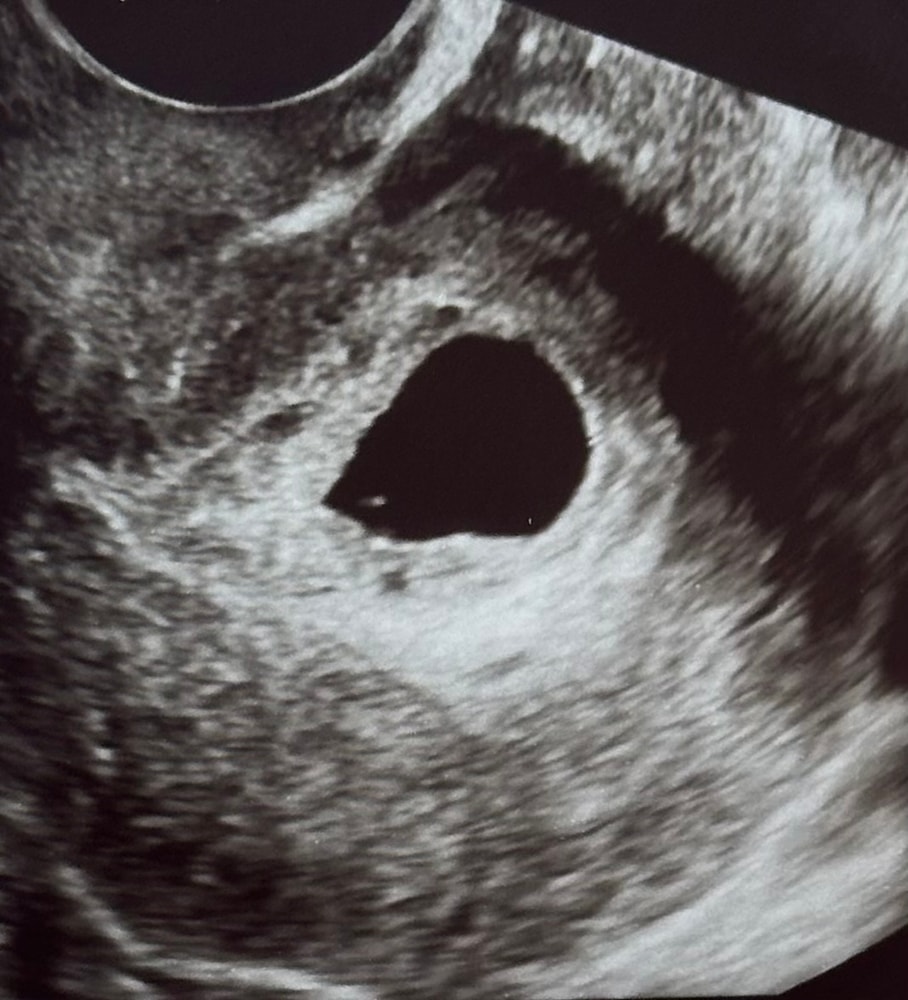

На УЗИ ПЯ 11мм, ЖМ 2мм, эмбриона нет. Не исключают анэмбрионию. Сказали проверить 18.07, если не появится - медикаментозный аборт. Направила своему гинекологу заключение, она к сожалению тоже не видит положительной динамики.